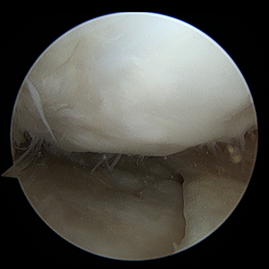

수술적 치료 : 무릎 연골재생술

초기

관절경적 미세천공술(Microfracture)

비교적 작은 연골 결손일 때, 체내 재생을 유도하는 단순하고 부담이 적은 수술입니다.

수술 방법 (어떻게 하는가)

1관절경(내시경)으로 병변 부위 관찰 손상된 연골을 정리

2뼈 표면에 작은 구멍 여러 개를 뚫어 미세천공 시행

3골수에서 재생 세포가 나오도록 유도

4세포들이 굳어져 섬유성 연골(질은 조금 떨어짐)이 새로 채워지는 방식

수술 전후 사례

수술 전

카티스템 수술

수술 후 1년